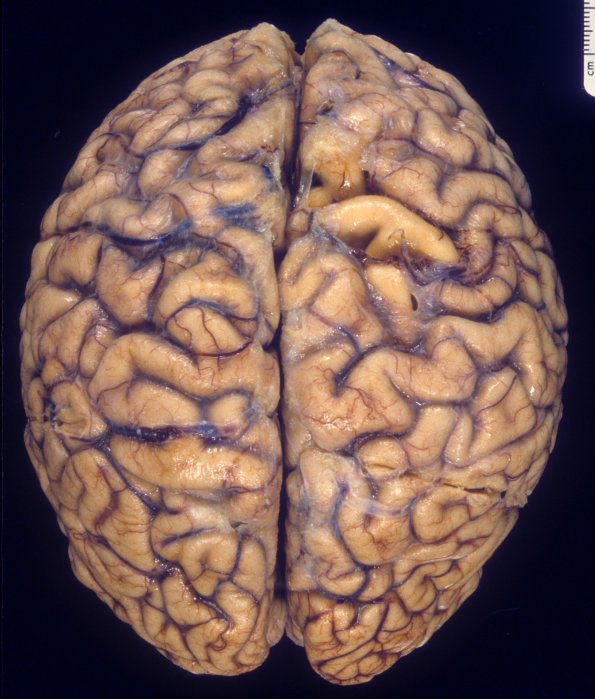

4A1-3 The brain (fresh weight 1330 grams) shows mild sulcal expansion and dilatation of the lateral ventricles, particularly the temporal horns (#4A3)